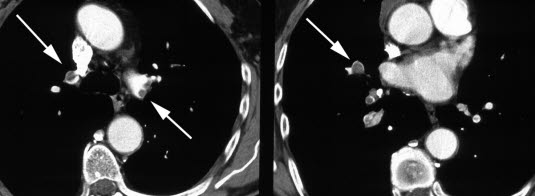

To CT-snitt etter intravenøs kontrastinjeksjon viser embolier (mørke) omsluttet av kontrast-tilblandet blod (lyst) i over- og underlappsarterier bilateralt (piler).